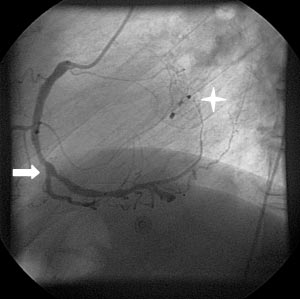

Im Mittelpunkt steht nach wie vor die Darstellung und Behandlung verengter Herzkranzgefäße (Abbildung 1). Insbesondere beim akuten Herzinfarkt ist die Koronarangioplastie sämtlichen anderen Therapieverfahren überlegen. Daraus leitete sich bereits frühzeitig ein Schwerpunkt der Düsseldorfer Kardiologie ab. Als Zentrum der Maximalversorgung wurde bereits seit Ende der neunziger Jahre eine leistungsfähige Infrastruktur aufgebaut, die Patienten in der Stadt und der Region einer umgehenden Herzkatheteruntersuchung beim Infarkt zuführt.